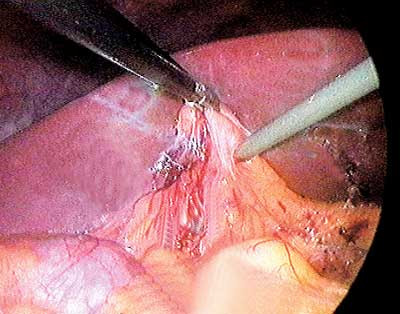

Under det laparoskopiske inngrepet ble det funnet en del adheranser i underkant av leveren, og disse ble delt. Operatøren bemerket at det var påfallende mye luft i tynntarmen. Noen vanlig galleblære kunne ikke påvises, men en del bindevev var lokalisert på galleblærens vanlige plass (fig 1). En strengformet struktur gikk herfra mot ductus choledochus. Den lot seg ikke kanylere med kolangiografikateter. Ingen ektopisk galleblære kunne påvises i leverhilus. Det nevnte bindevevet ble fjernet og inngrepet avsluttet. Operasjonspreparatet målte 3,5 ¥ 0,8 cm, og den mikroskopiske undersøkelsen viste: «Sparsom mengde bindevev og kjertler som kan representere vev fra galleblære, det hele mest forenlig med galleblæreagenesi» (Patologisk-anatomisk avdeling, Universitetssykehuset Nord-Norge). Pasienten fikk noen måneder senere utført endoskopisk retrograd kolangiografi (fig 2). Fem måneder etter operasjonen var ALAT 78 U/l og GT 95 U/l, og bilirubin- og ALP-verdiene var normale. Han ønsket på det tidspunktet ikke noe videre utredning.

I forbindelse med etterundersøkelse av galleopererte personer i Rana sykehus’ område besvarte pasienten et spørreskjema fem år etter operasjonen. Han anførte da at han ønsket videre undersøkelser på grunn av økende plager. Plagene har endret karakter og består i akutte, knivstikksliknende smerter oppunder høyre kostalbue, og er nå uten klar relasjon til måltidene. Men han blir lett kvalm hvis han spiser fet mat. Under anfall får han vondt når han trekker pusten dypt. Slike anfall kan inntreffe en gang hver eller hver annen uke. Han har regelmessig avføring, men noen ganger er avføringen mer gulaktig på farge og flyter opp i toalettskålen. Klinisk undersøkelse har vært upåfallende. Blodprøvene har vist stigning av ALAT til 105 U/l og GT til 114 U/l, mens bilirubinnivået er 14 U/l og ALP-nivået 131 U/l. MRCP (fig 3) viser slanke galleganger og ingen mistanke om steiner. Røntgen tynntarm med sonde viser normale forhold, og det er ingen tegn til trange partier eller malrotasjon. Han har stabil vekt og bruker ingen medikamenter. Han har ikke sur dyspepsi for tiden og ønsker ikke å gjennomgå gastroskopi.